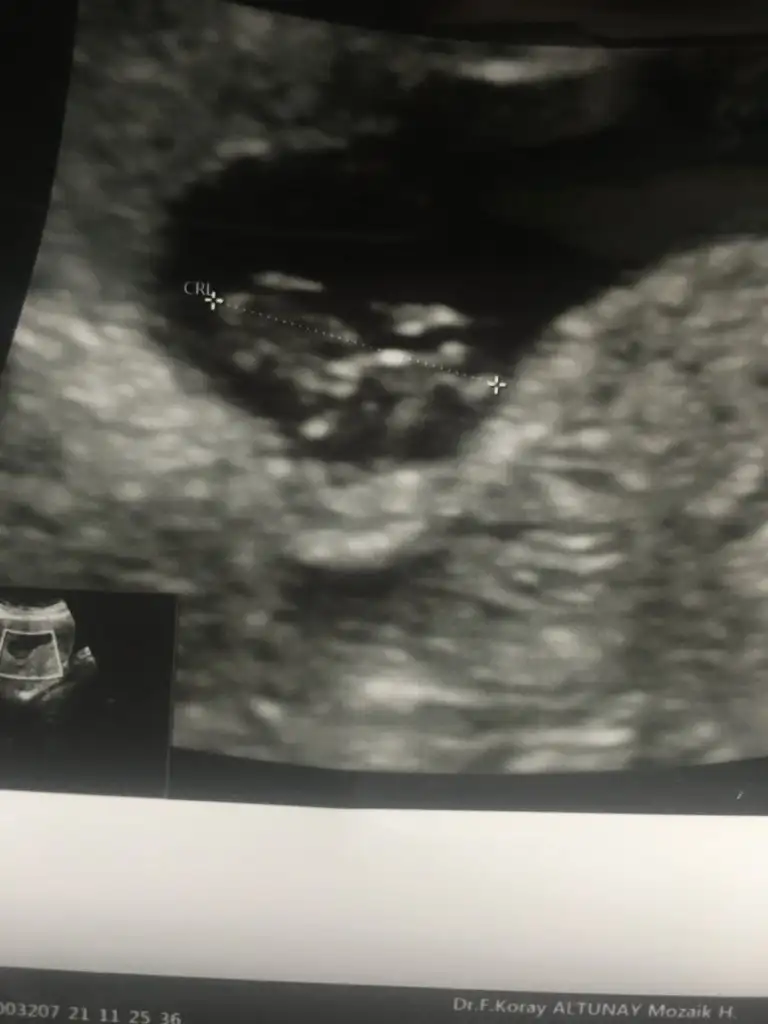

Canım bakar mısın 14. Haftada

Eklentiler

• 91111F39-1F06-449C-B28B-65C4846CABAC.webp

91111F39-1F06-449C-B28B-65C4846CABAC.webp

40 KB · Görüntüleme: 66